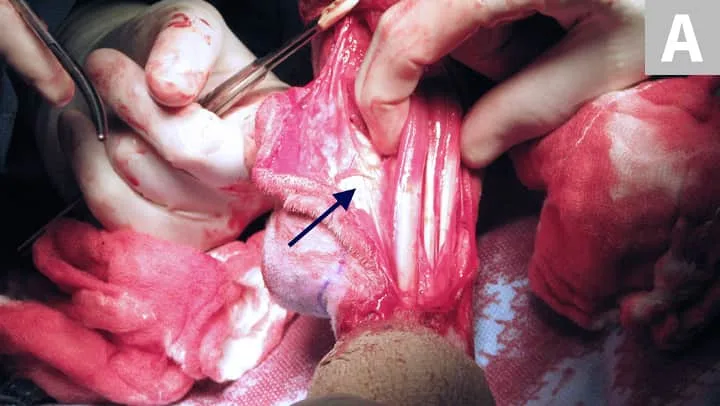

Osteosarcoma (OSA) is the most common primary bone tumor in dogs.5 Unfortunately, most cases are not cured with surgery because of the high risk for metastatic disease.5 Patients should be staged for gross metastasis to lung or another bone before surgery (Figure 2). Staging methods vary depending on clinician preference, but 3-view thoracic radiographs and/or thoracic CT and bone scan are recommended.6 Limb amputation is the most commonly performed surgical treatment; major benefits include removal with wide margins of the tumor, removal of the source of pain, and removal of potential for ongoing metastasis.

(A) Radiograph of a distal radial osteosarcoma. Centered at the distal metaphysis of the radius, there is evidence of permeative and moth-eaten lysis. There is also concurrent ill-defined periosteal proliferation consistent with an aggressive bone lesion. (B) CT scan of distal radial osteosarcoma in the same patient. Coronal view of limb in bone window. There is more evidence of geographic bone lysis and evidence of periosteal proliferation. Consistent with an aggressive bone lesion. (C) Bone scan of the distal radial osteosarcoma in the same patient. Note the increased uptake of radiopharmaceutical in the distal radius of the patient (arrow).